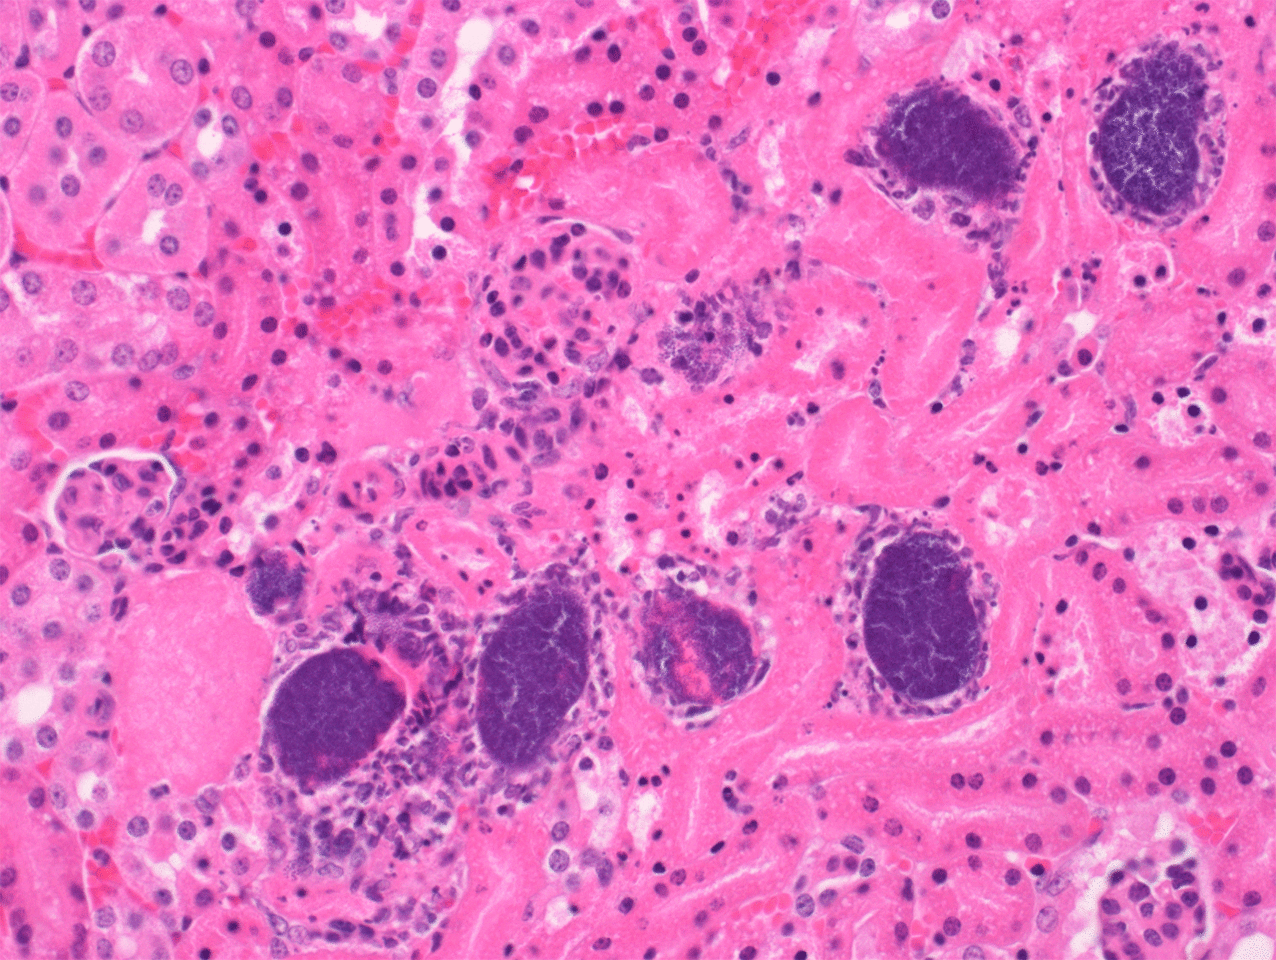

Our most recent discovery, detailed in the Nature Communications paper just published, started several years ago when Dr. Jessica (Jess) Sheldon, then a doctoral student in Dr. David Heinrichs’ laboratory, was generating mutants in Staphylococcus aureus. This bacterium is a notorious human and animal pathogen that causes a variety of different conditions, including life-threatening pneumonia, endocarditis (heart infection) and sepsis; varieties of this bacterium can be antibiotic resistant, exemplified by methicillin resistant S. aureus (MRSA). Jess observed that some of her mutants severely aggregated when grown in the presence of serum. This aggregation, or “clumping”, hadn’t been seen before and, although shortly thereafter Jess would leave the lab to commence post-doctoral work, her observation peaked Dr. Heinrichs’ interest enough that he decided to pursue the observation. Dr. Heinrichs spent a lot of time at the bench over the next 8 months and, with the help of various students, discovered that the phenotype was due to the unanticipated selection for spontaneous off-target mutations in the S. aureus genome. All mutations occurred in the purR gene encoding the repressor of purine biosynthesis. Purines are chemicals that are essential for DNA synthesis and energy generation. Working closely with Dr. Ron Flannagan in the lab, Dr. Heinrichs further showed that, curiously, inactivating mutations in purR caused S. aureus to become highly virulent in mouse models of infection. The lab spent the next year exploring different aspects of purR and S. aureus biology and the link to hypervirulence. Working side-by-side with undergraduate student Brigid Sterling, Dr. Heinrichs linked the clumping phenotype in purR mutants to the requirement for fibronectin binding proteins (FnBPs) in S. aureus.

Dr. Mariya Goncheva, a PDF who arrived in the lab in late 2017, took over the project, and began to puzzle out the relationship between PurR and FnBPs and how they were contributing to differences in the ability of S. aureus to cause severe disease. She spent the next year or so figuring out that PurR in fact represses expression of FnBPs, and this dampens the pathogenic potential of S. aureus; purR mutants result in aberrant overexpression of FnBPs, causing the cells to aggregate with fibronectin in serum and this correlates with hypervirulence. Indeed, there was protection from purR hypervirulence with anti-FnBP antibodies, which provides new insight into S. aureus infection in humans and how prior exposure can be beneficial.